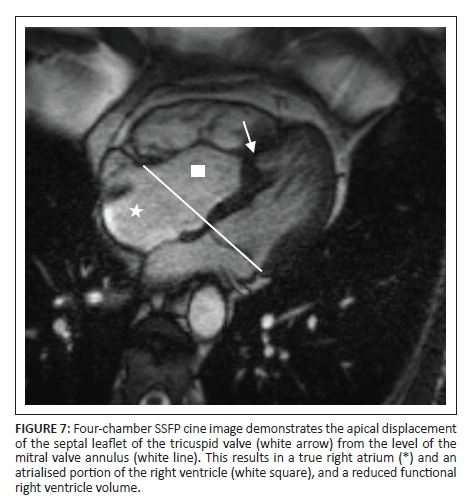

Attachment abnormalities

The most common attachment abnormality of the valves is Ebstein's abnormality, where there is apical displacement of the implantation of the septal leaflet of the tricuspid valve (Figure 7). The degree of apical displacement varies with Ebstein's abnormality and is classified as abnormal if apical displacement of the septal leaflet of more than 8 mm/m2 is present.6 This results in part of the right ventricle being incorporated into the right atrium and subsequently increases the right atrial size and decreases the functional right ventricle volume.